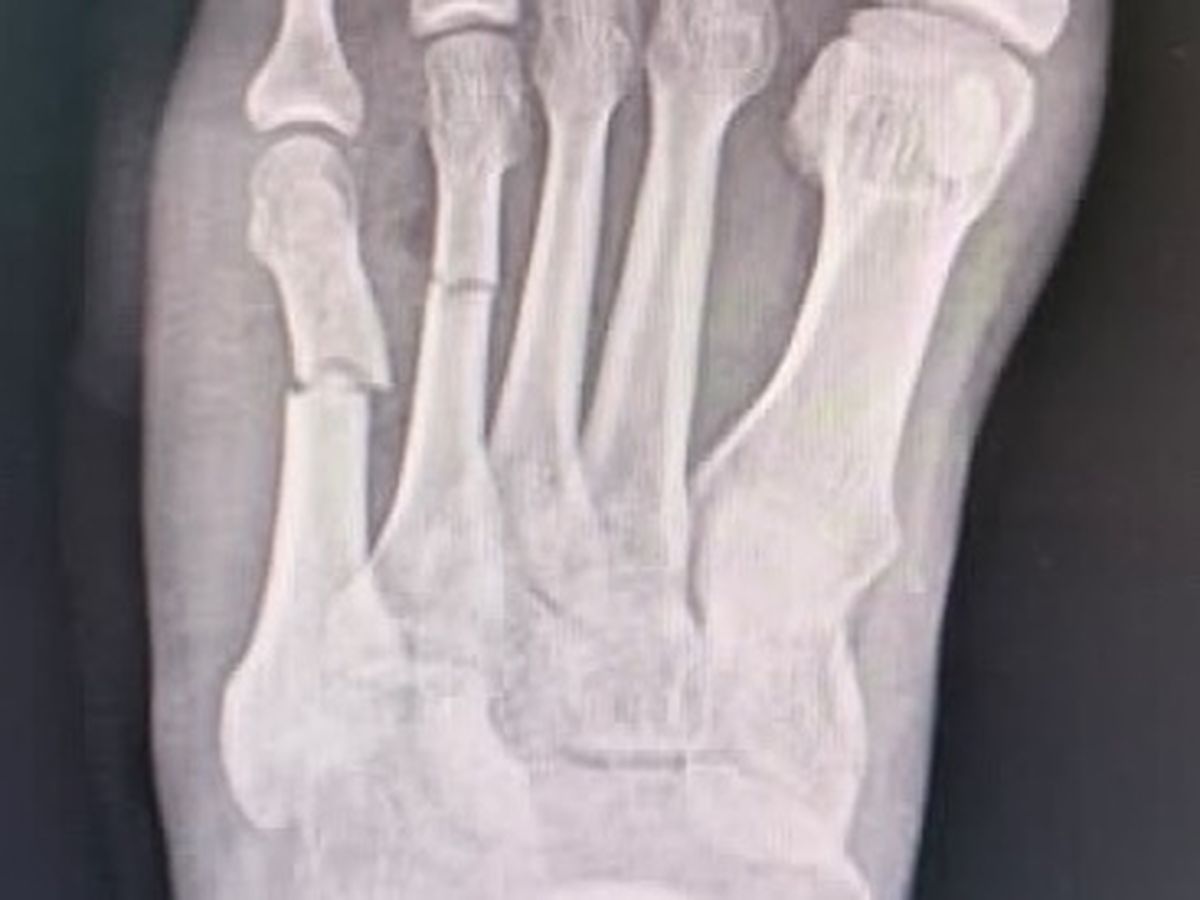

Hi everyone. It’s embarrassing to have to do this but I’ve had a motorcycle accident in Koh Phangan, Thailand and have been quite badly injured. It’s mostly superficial but I have had to have 8 stitches and have broken 2 metatarsal in my left foot that needs operating on. I was originally quoted 400,000 baht (around £10,000) so I was forced to discharge myself and get a boat to Koh Samui to a government hospital where I have been quoted around half of that. I’ve spent everything I have on medical bills and at this point I don’t even have enough to go and have my stitches taken out. I know it’s a lot to ask but if anybody could help in the smallest way possible I would appreciate anything at all. Thank you and sorry to come to you cap in hand. I’m just 6000 miles away from home with no money left. Thank you again guys ❤️